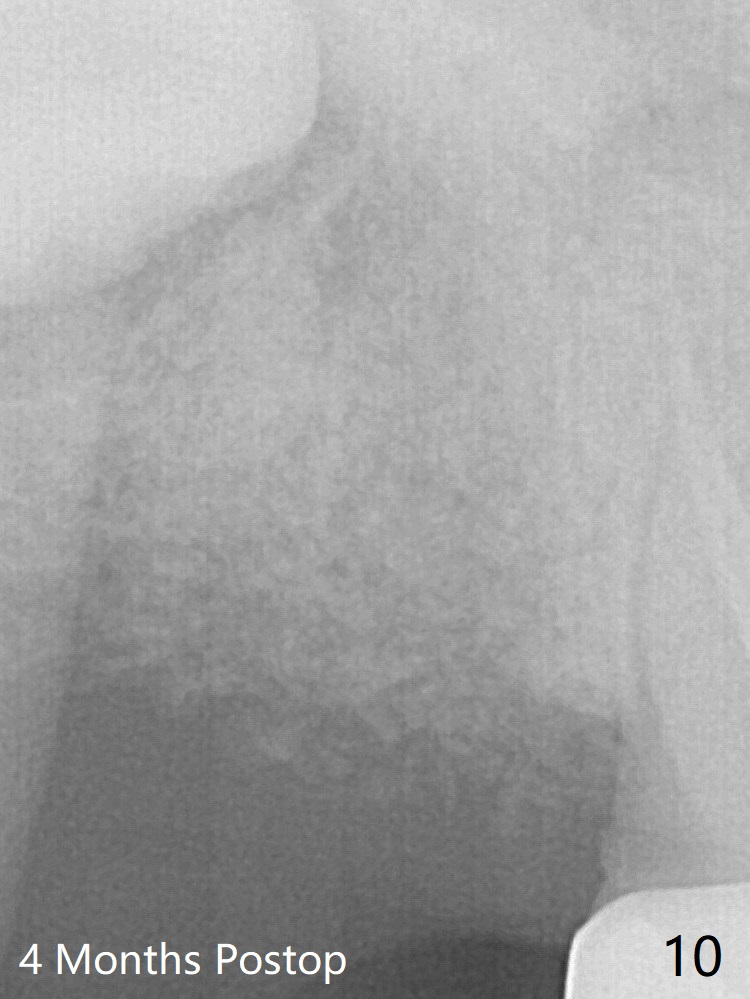

The pattern of bone graft granules changes in 4 months (compare Fig.8,10).